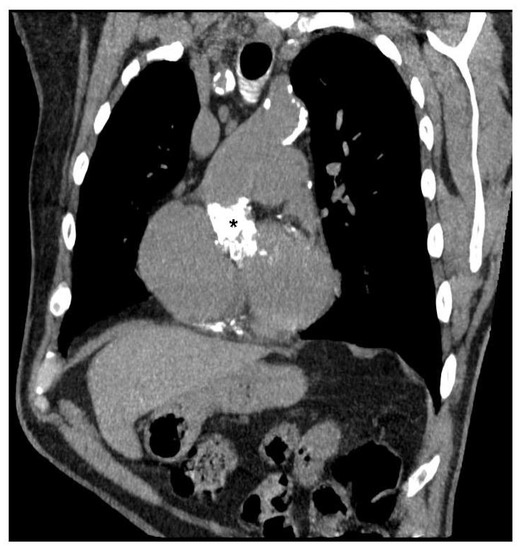

- Ravenni, G.; Pratali, S.; Scioti, G.; Bortolotti, U. Total calcification of an aortic homograft used as aortic root replacement. J. Cardiovasc. Med. 2011, 12, 191–192. [Google Scholar] [CrossRef]